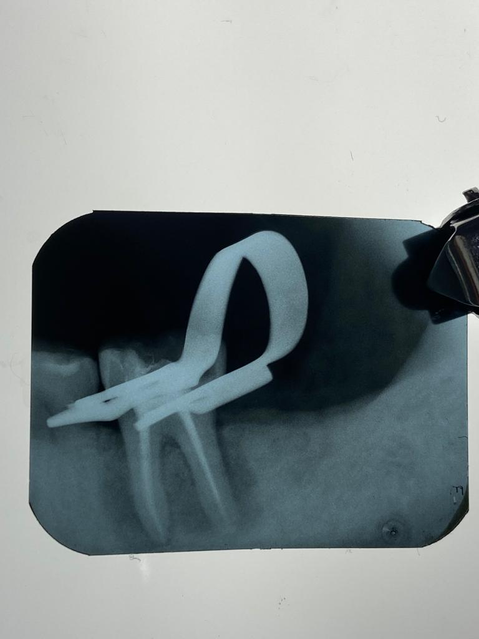

Tratamento de canal dói?

Não. Temos tecnologia adequada para cada procedimento. Na verdade o que dói é não fazer o tratamento de canal. A dor de dente é causada pela infecção da polpa e, quanto mais tempo o paciente demorar a fazer do procedimento, maior poderá ser esse incômodo.